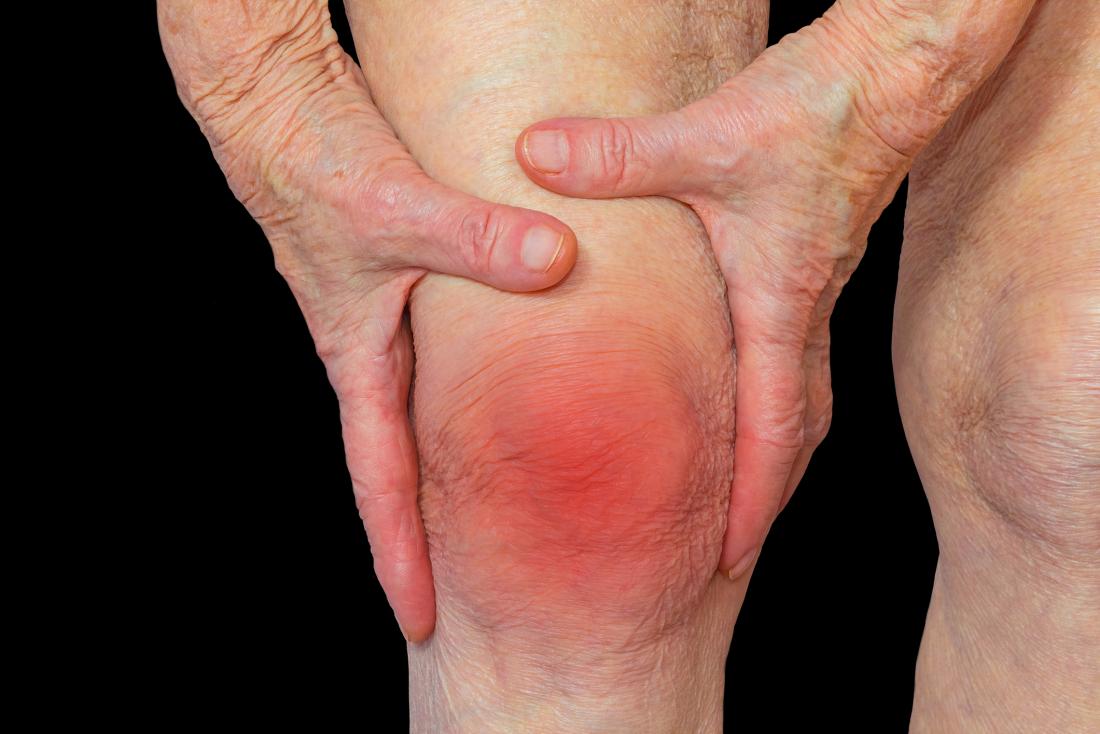

For people diagnosed with arthritis, pain is generally categorized as chronic that usually lasts for at least three months. Many patients describe this type of pain as aching, dull, burning or throbbing, which is comparable to a boa constrictor squeezing the affected joints. However, though arthritis can be well-managed by different treatment options, pain can also be sudden and unpredictable. This acute episode of pain and inflammation, referred to as arthritis flare, is oftentimes triggered by infection or stress. Though acute arthritic pain is only temporary, it can significantly affect our everyday life in terms of our capacity to perform daily tasks.

One of the most common treatment options for arthritis is over-the-counter pain medication. However, this approach may not always address the problem effectively and may also pose certain risks. Hence, some patients skip the pills and prefer to try other alternative methods such as topical medications, exercise, physical therapy, meditation, acupuncture and heat or cold application.